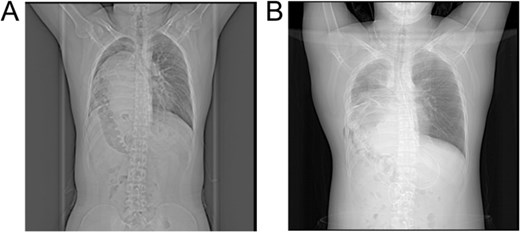

The patient was a 19-year-old male who experienced shortness of breath following physical activity 3 months earlier. Further examination identified a diaphragmatic hernia, and on 8 July 2024, he sought treatment in the Department of Thoracic Surgery at a hospital. Physical examination showed dullness to percussion in the right thoracic cavity from the second to sixth intercostal spaces, with an elevated liver dullness border. CT imaging confirmed a right-sided Bochdalek hernia with partial herniation of the liver into the thoracic cavity, compression, and atelectasis of the right lung, and mediastinal shift (Fig. 1). Upper gastrointestinal X-ray with contrast identified a filling defect in the duodenal bulb, mucosal irregularity, and proximal jejunum displacement in the upper right abdomen, suggestive of malrotation. A significantly elevated right hemidiaphragm further indicated the presence of a diaphragmatic hernia.

X-ray images: (A) Preoperative X-ray showing a suspected liver mass occupying the right thoracic cavity; (B) Postoperative X-ray showing re-expansion of the right lung and the liver returned to the abdominal cavity.